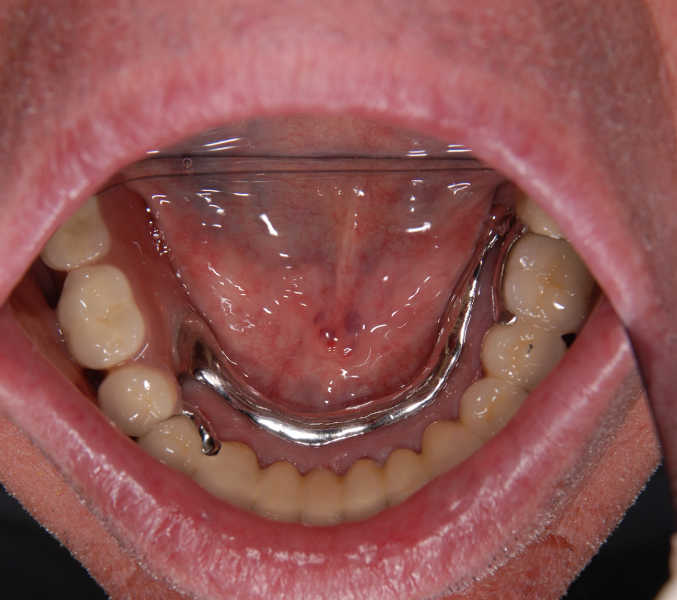

Intra oral view after treatment